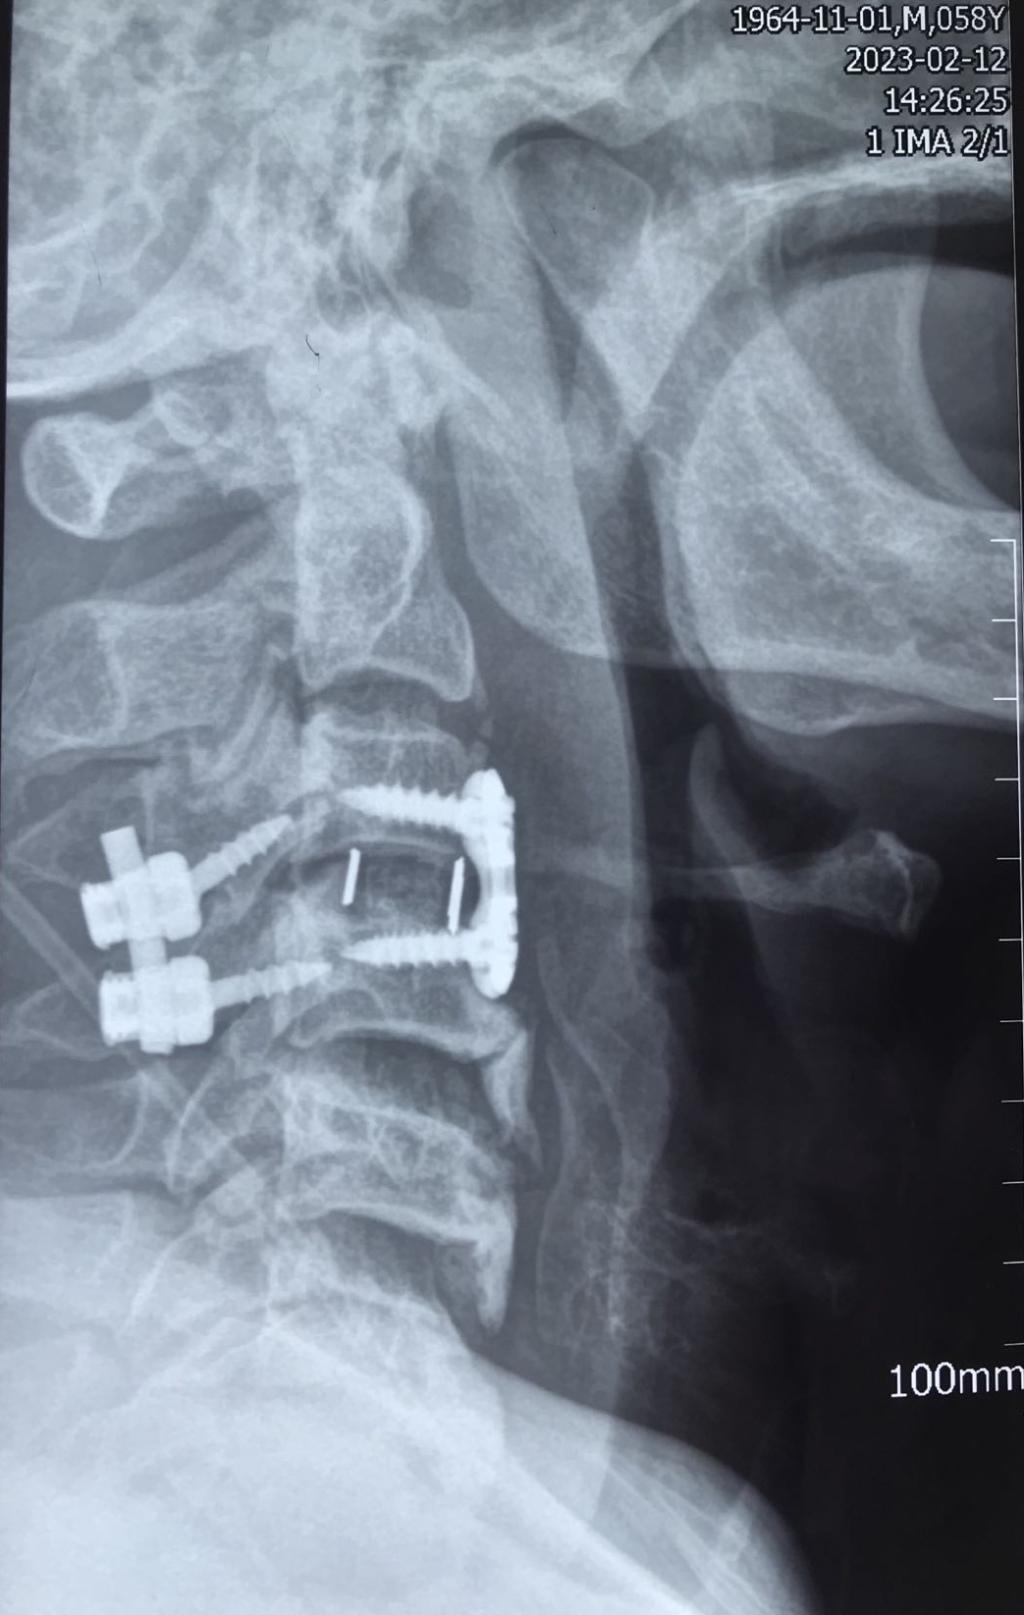

经过有序准备,为患者先行颈后路减压,解锁关节突绞索,牵引复位,使用颈椎侧块螺钉固定,同时椎板间植骨融合。随后再将患者转为仰卧位,再行颈前路脱位椎体的间盘摘除,融合器植入,钢板螺钉固定,历时3小时,顺利结束。患者术后恢复良好,肢体功能状态较术前改善显著,上肢抽痛症状消失,肌力已达4-5级,患者及家属对治疗效果颇为满意。